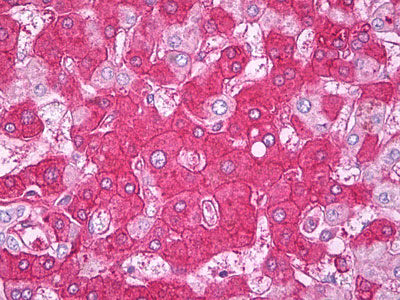

Anti-Factor H antibody IHC of human liver. |